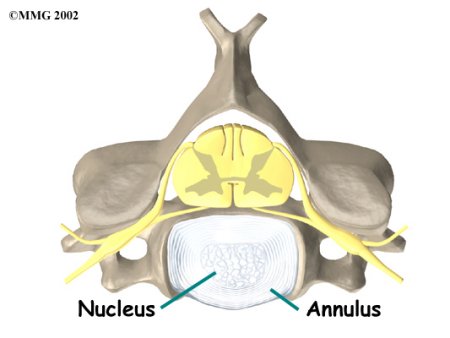

An intervertebral disc is made of connective tissue. Connective tissue is the material that holds the living cells of the body together. Most connective tissue is made of fibers of a material called collagen. In some cases, the collagen fibers join together to form a structure like a rope. In other cases, the fibers are arranged like a piece of cloth, or knitted materials such as you find in a sweater. The disc is a specialized connective tissue structure that separates the two vertebral bodies of the spinal segment. The disc normally works like a shock absorber. It protects the spine against the daily pull of gravity. It also protects the spine during activities that put strong force on the spine, such as jumping, running, and lifting.

An intervertebral disc is made up of two parts. The center, called the nucleus, is spongy. It provides most of the ability to absorb shock. The nucleus is held in place by the annulus, a series of strong ligament rings surrounding it. Ligaments are strong connective tissues that attach bones to other bones.

Two Parts of Intervertebral Disc